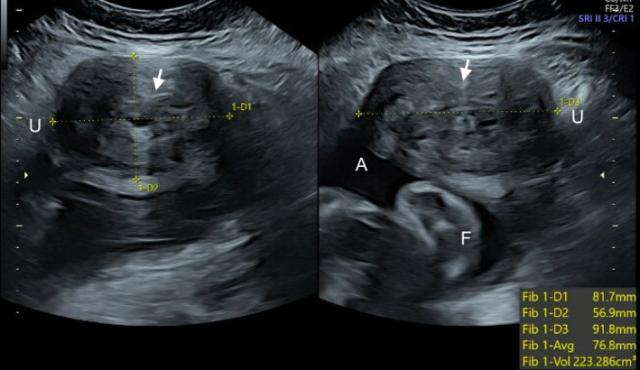

Медицинские аспекты мекония в околоплодных водах